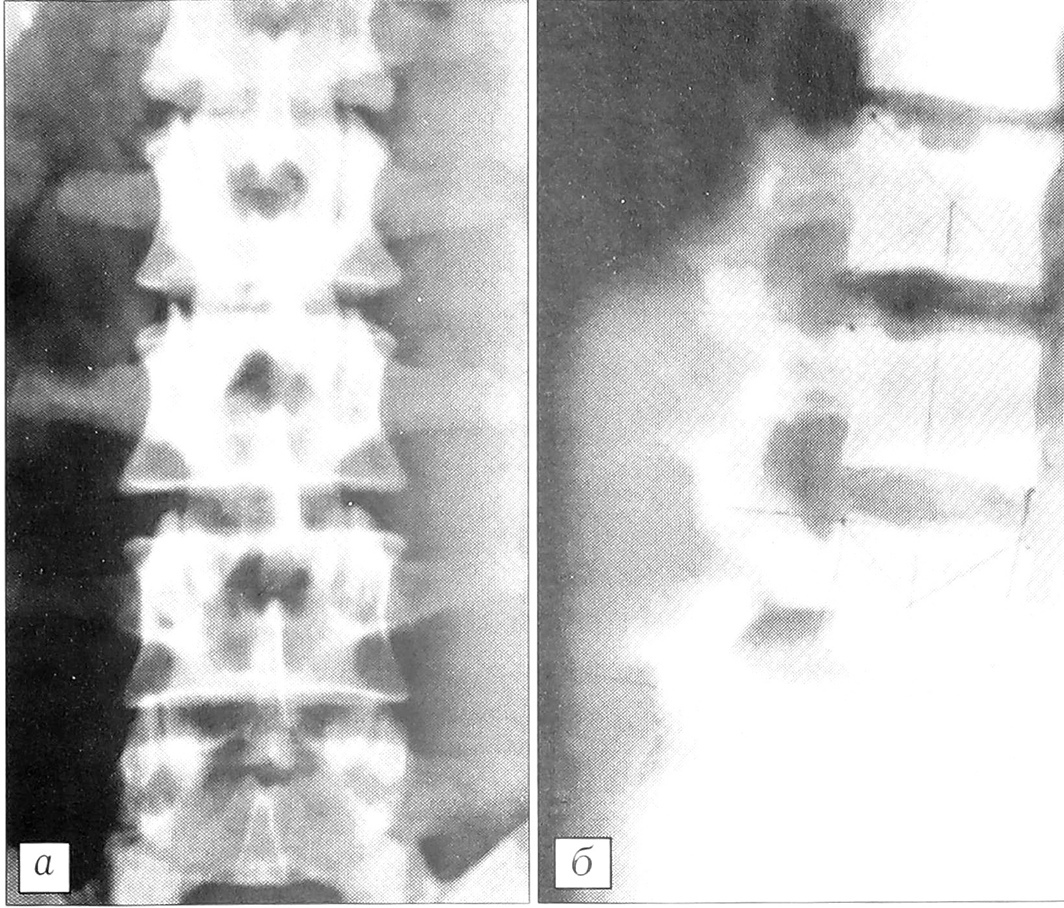

Рис. 10. Рентгенограммы поясничного отдела позвоночника больных с асимметричной гипо- и гиперплазией суставных отростков.a — асимметричная гипоплазия суставных отростков Ы~3 позвонков, аномалия тропизма в сегменте L3-4; б — асимметричная гиперплазия суставных отростков L3-5 позвонков, сагиттализация суставных фасеток в сегментах L2-3, L4-5. Полисегментарный спондилоартроз.